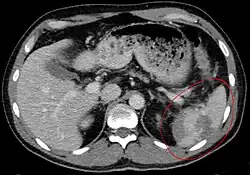

Un scanner de l'abdomen peut donner un aperçu plus complet des blessures spléniques et autres, pouvant montrer une fracture, des lacérations ou un hématome sous-capsulaire. La gravité des lésions peut être ainsi classée[9] ce qui permet une optimisation de la prise en charge et une diminution sensible de la nécessité d'une prise en charge chirurgicale[10].